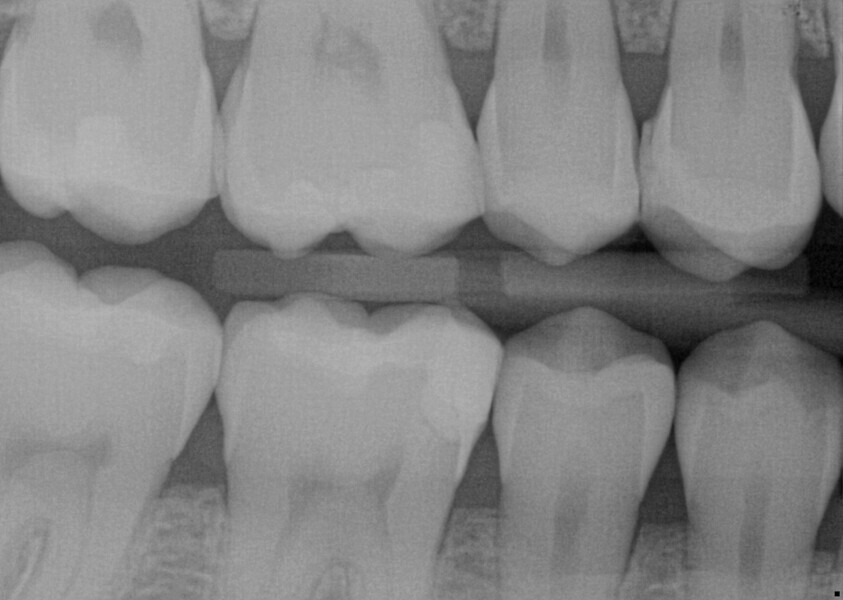

Fig. 20: Bitewing radiograph of the existing composite restorations.

A 23-year-old female patient presented with cold sensitivity of the teeth in the maxillary right posterior sextant. Examination noted old composite fillings in the molars and premolars and recurrent caries on each tooth (Fig. 19). A bitewing radiograph was taken to evaluate the extent of the recurrent caries and the dimensions of the composite restorations (Fig. 20). Owing to the dimensions of the restorations and caries, inlay and onlay restorations were suggested to restore the teeth and preserve tooth structure as an alternative to complete crowns. The patient’s questions were answered, and she agreed to the proposed treatment. She was informed that the treatment could be completed in a single appointment utilising 3D printing for restoration fabrication. Time in the schedule permitted treatment to be performed during that same appointment. Our intent is to provide conservative restoration with superior accuracy and definition compared with milling, as well as better predictability and mechanical properties compared with direct resin composite restorations.